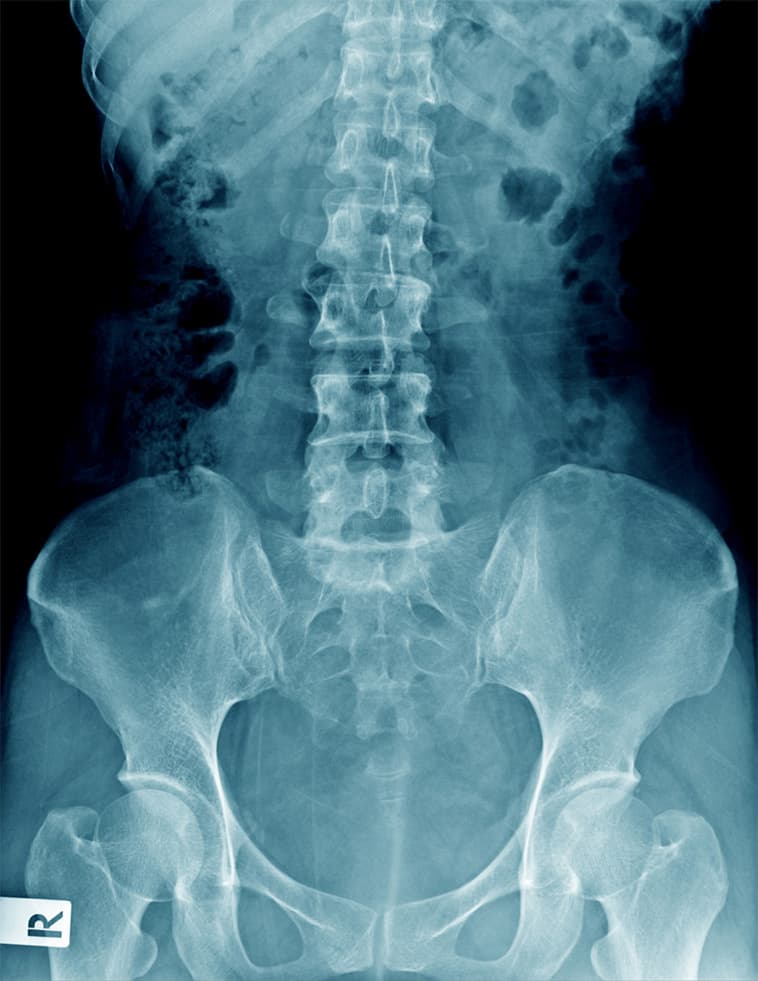

La coxartrosi, nota anche come artrosi dell'anca, rappresenta una condizione patologica degenerativa, cronica e progressiva che coinvolge la cartilagine che riveste le estremità ossee dell'articolazione coxo-femorale.

L'evoluzione progressiva della degenerazione articolare conduce all'usura della cartilagine, causando dolore e rigidità. Tali sintomi si accentuano in relazione all'avanzamento del processo artrosico.